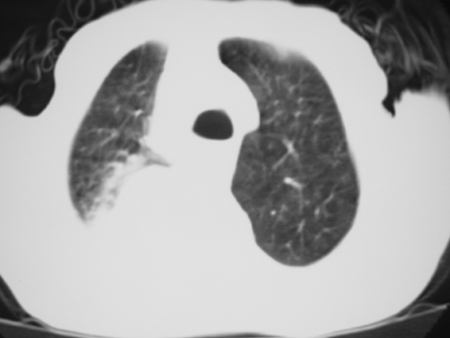

男77岁,胸痛就诊

右侧胸腔积液,部分包裹,右下肺膨胀不全,右下肺感染。

考虑右肺门占位并下叶不张 右胸包裹积液

右侧胸腔积液,部分包裹,右下肺膨胀不全